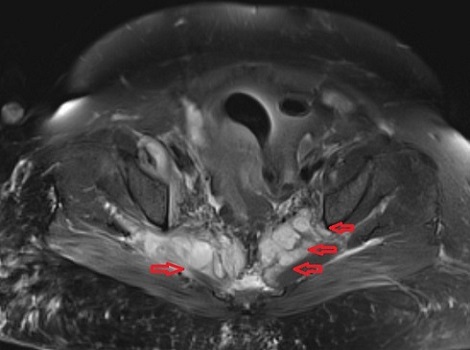

Στις εικόνες της μαγνητικής διακρίνονται τα διάφορα αποστήματα (κόκκινα βέλη) στους μύες (λαγνοψωίτες, απιοειδείς και δεξιό γλουτιαίο).

Το απόστημα του δεξιού λαγονοψωίτη καταλάμβανε ολόκληρη την έκταση του μυός. Τέλος, σημαντικό νέο εύρημα ήταν η παρουσία επισκληρίδιου εμπυήματος το οποίο κρίθηκε ότι δεν χρειάζεται χειρουργείο.